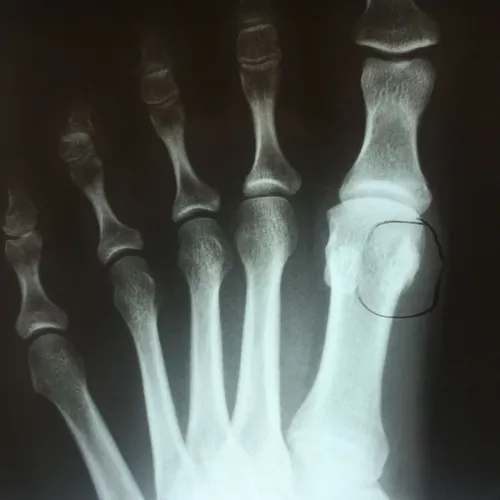

Patient had chronic pain after comminuted sesamoid fracture. After conservative care, patient had total sesamoidectomy and is pain free 3 months postop

Pre and Postop Tibial Sesamoidectomy